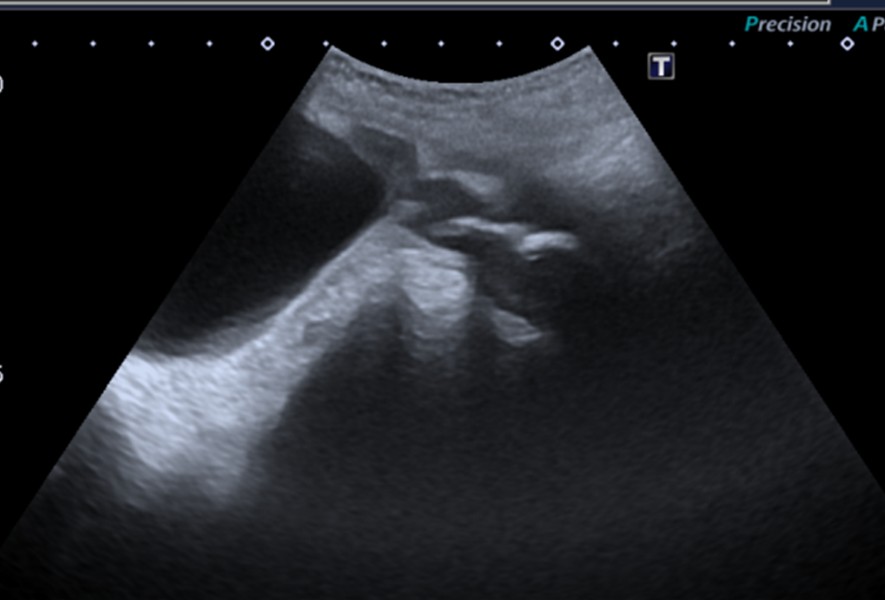

La ecografía ginecológica informa vejiga ampliada de contornos irregulares lateralizada a la derecha. En línea media, en probable topografía de vagina, se observan imágenes ecogénicas calcificadas con sombra acústica. La vagina mide 38 x 23 x 27mm (Imagen 6).

a) Ecografía que evidencia imágenes hiperecogénicas en topografía vaginal.